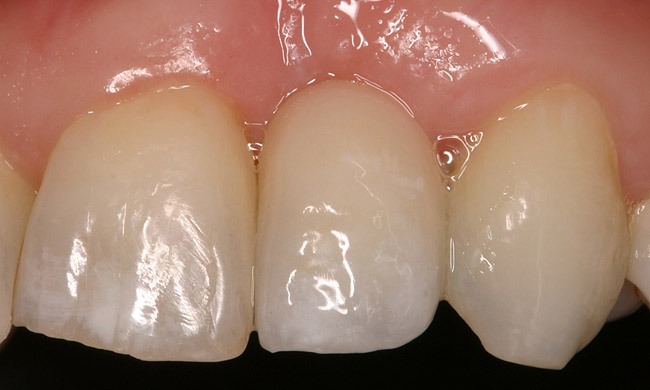

Figure 6d Completed treatment: revised RCT, zirconium post/pressed ceramic core cemented with Panavia 21¬Æ Resin Cement (Kuraray Dental). All-ceramic full-coverage crown cemented with Kerr NX3 Nexus¬Æ Third Generation Dual Cure Resin cement. Implant therapy not indicated.

Figure 6d

Figure 6e  Completed treatment: revised RCT, zirconium post/pressed ceramic core cemented with Panavia 21¬Æ Resin Cement (Kuraray Dental). All-ceramic full-coverage crown cemented with Kerr NX3 Nexus¬Æ Third Generation Dual Cure Resin cement. Implant therapy not indicated.

Figure 6e

Figure 6f  Completed treatment: revised RCT, zirconium post/pressed ceramic core cemented with Panavia 21¬Æ Resin Cement (Kuraray Dental). All-ceramic full-coverage crown cemented with Kerr NX3 Nexus¬Æ Third Generation Dual Cure Resin cement. Implant therapy not indicated.

Figure 6f